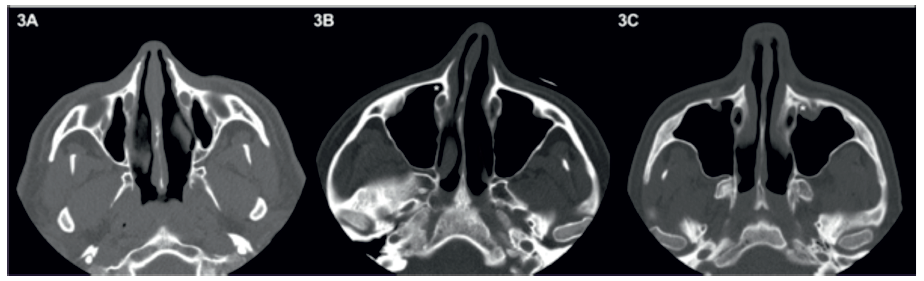

O RPL foi considerado como estando ausente quando a parede anterior do canal nasolacrimal (CNL) se encontrava adjacente à face posterior da parede anterior do seio maxilar (Figura 3A). Nos casos em que este se encontrava presente, este foi classificado como anterior caso parte do RPL se encontrasse anteriormente ao CNL ou como lateral caso o RPL se encontrasse totalmente lateralmente ao CNL (Figuras 3B e 3C).

Figura 3 Em (A) o canal nasolacrimal encontra-se adjacente à parede anterior do seio maxilar, não existindo, por isso, recesso pré-lacrimal. Em (B) e em (C) o recesso pré-lacrimal (*) encontra-se presente, tendo uma localização anterior e lateral, respetivamente.